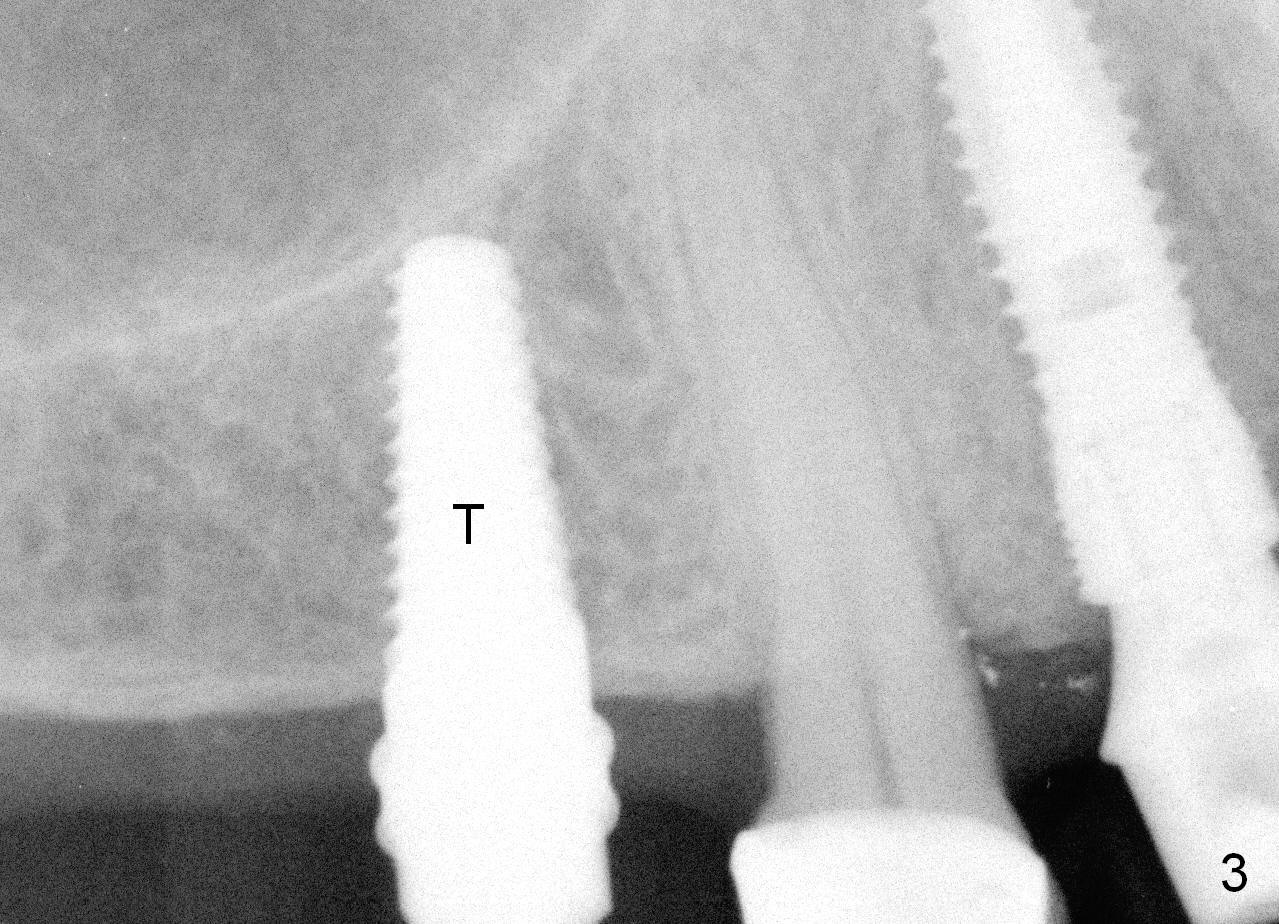

Both the teeth #30 and 31 are supraerupted. There is no restorative space for #2. So #3 implant will support the most distal crown. A 4 mm tissue punch is used, followed by a 2 mm pilot drill. Bone type is 3. A parallel pin shows that the trajectory needs to be adjusted (Fig.2). By the time a 4.5 mm tap is placed, the trajectory is within normal limit (Fig.3,4 T). A 5.3x10 mm implant is placed with insertion torque > 60 Ncm (Fig.5; *: sinus lift). After insertion of an abutment, an immediate provisional is fabricated with intention to prevent further supraeruption of the tooth #30 during #3 implant osteointegration.